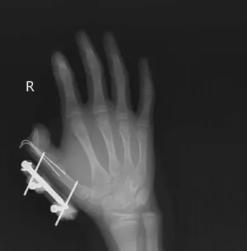

前段时间,湖南的一名 14 岁的小孩在爸爸网购冰激凌的箱子里发现了用于冷藏的干冰,以为是玩具,便捏在手里反复摇晃。结果密封袋里的干冰突然爆炸,小朋友的右手瞬间鲜血直流,拇指虎口处被撕开一道约 10 厘米的伤口,拇指骨折。

图片来源于网络